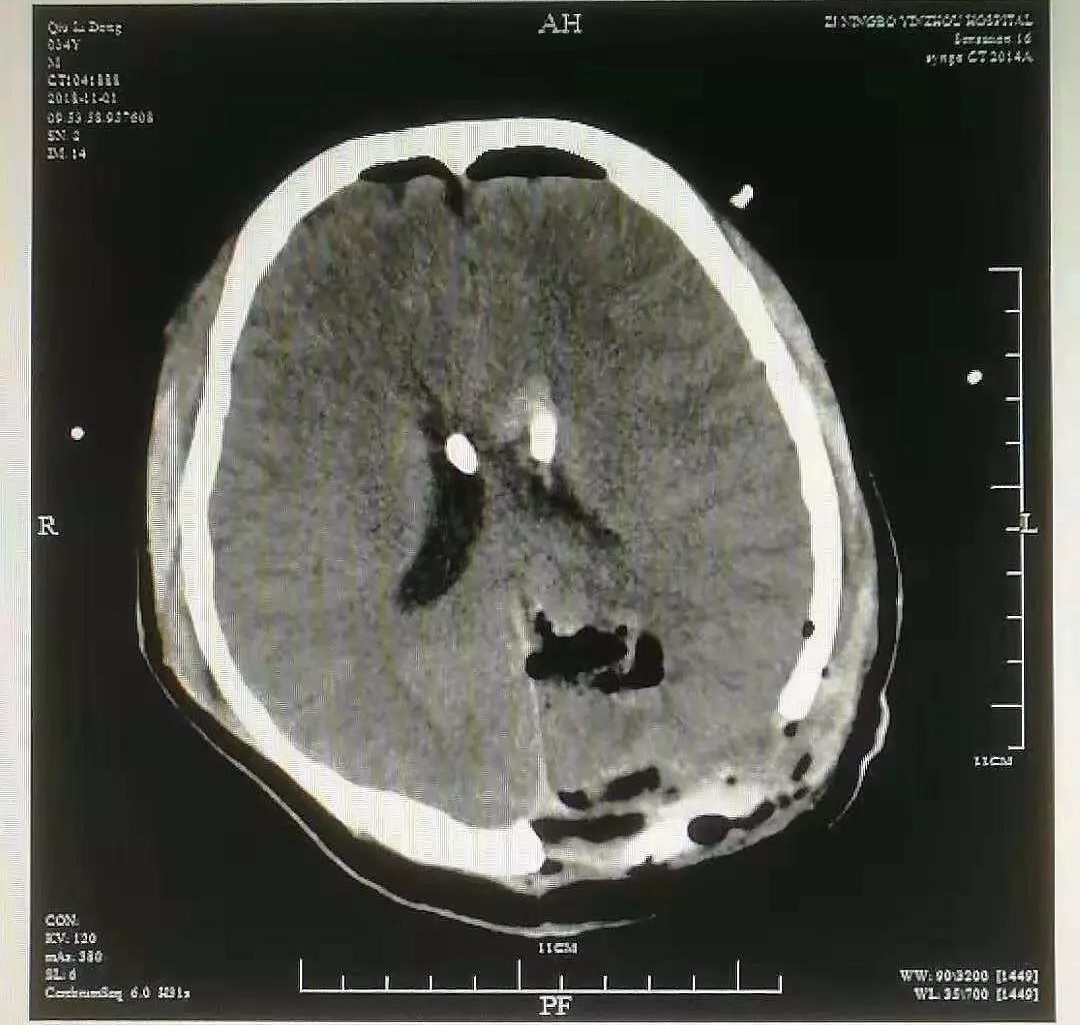

术后影像

小王的脑出血就是因为颅内动静脉畸形引起的,近年来,医院还接诊了多例类似患者。

高峰介绍,脑动静脉畸形多见于年轻人,以20岁-30多岁青壮年发病率最高,男性多于女性。病变可发生于脑的任何部位,但以顶叶最多,其次为额叶及颞叶。发病时可表现为头疼、肢体偏瘫、癫痫、恶心呕吐、意识障碍等。手术切除是治疗颅内动静脉畸形最彻底的方法,可以消除病变出血的风险,改善脑血供,还能控制癫痫发作。对于病变小于3cm的,位于重要功能区,或者位置深在,不能手术的患者,可以选择立体性放射治疗。